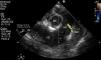

Lactante de 6 meses de vida, asintomático, remitido a consulta de cardiología pediátrica para estudio de soplo. En la exploración destaca soplo sistólico II/VI en borde paraesternal izquierdo. El ECG muestra onda Q en I y aVL. Se realiza ecocardiografía transtorácica (donde se observa función biventricular conservada con diámetros telediastólicos aumentados (Z score: +2,99), hiperrefringencia endomiocárdica, arteria coronaria derecha dilatada (3,6mm, Z score +3; [fig. 1]) y transesofágica (fig. 2): por encima del plano valvular pulmonar y en cara lateral del mismo se visualiza un vaso que drena en el tronco pulmonar, recogiéndose su flujo en diástole).